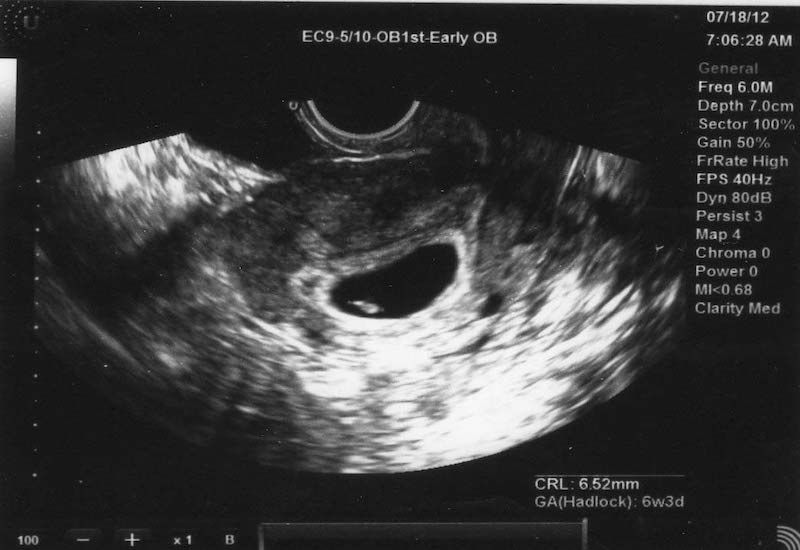

Nhờ sự tiến bộ của công nghệ y học, mẹ bầu có thể thực hiện siêu âm khi thai nhi mới chỉ đang ở tuần 4. Mặc dù không thể nhìn rõ em bé nhưng hình ảnh siêu âm thai 4 tuần tuổi sẽ phần nào thỏa mãn được sự tò mò, háo hức của người làm cha làm mẹ. Kết quả siêu âm thai 4 tuần sẽ có các thông tin như kích thước túi thai hay vị trí thai làm tổ. Tuy vậy, vẫn chưa có gì chắc chắn để khẳng định thai 4 tuần đã vào tử cung chưa.

Để mô tả chính xác nhất, phôi thai lúc này chỉ như một chú nòng nọc siêu nhỏ với phần đầu lớn, phần thân nhỏ cùng các chồi xung quanh (tay, chân sau này). Các chỉ số khác chỉ chính xác ở mức tương đối khi dựa vào hình ảnh thai nhi 4 tuần tuổi. Bác sĩ sẽ hẹn mẹ lịch khám lại ở những tuần tiếp theo để thấy thai nhi rõ nét và có nhiều thông tin hơn.

Kết quả siêu âm thai 4 tuần sẽ có các thông tin như kích thước túi thai hay vị trí thai làm tổ. Tuy vậy, vẫn chưa có gì chắc chắn để khẳng định thai 4 tuần đã vào tử cung chưa. Mỗi mẹ có một thể trạng khác nhau nên thời gian thụ thai, làm tổ sẽ nhanh hay chậm không giống nhau.